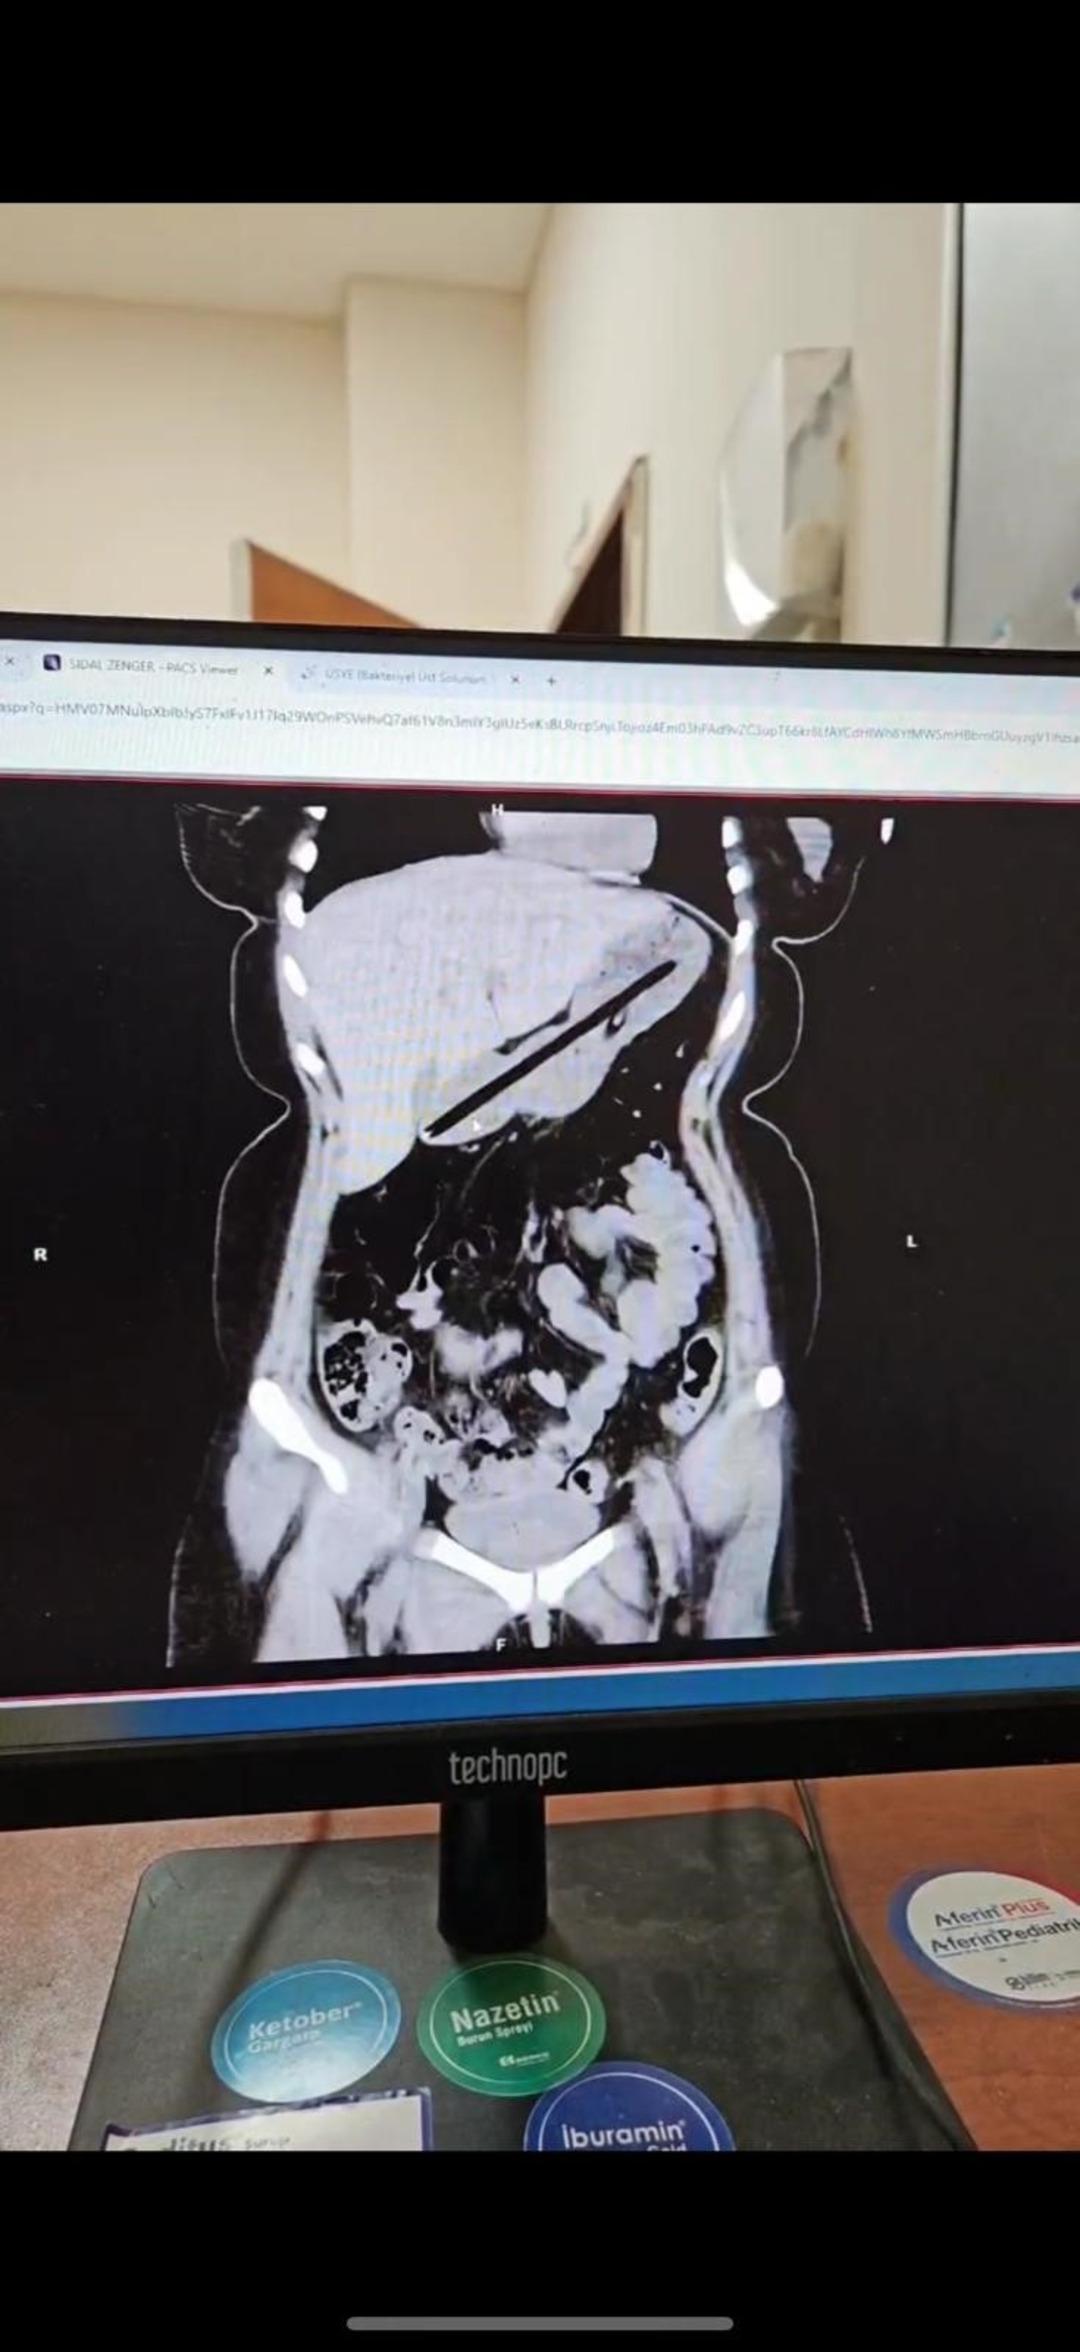

Ailesi tarafından Ağrı Eğitim ve Araştırma Hastanesi Acil Servisi'ne getirilen hastanın midesinde yabancı cisim tespit edildi.

Genel Cerrahi ekibince ertesi gün gerçekleştirilen yaklaşık bir buçuk saat süren endoskopi operasyonuyla genç kadının midesinden biri kurşun, diğeri tükenmez olmak üzere iki kalem çıkarıldı.

Operasyonu gerçekleştiren Dr. Öğretim Üyesi Adem Aslan, ilk kez böyle bir vakayla karşılaştıklarını belirterek, "22 yaşındaki bayan hastamız kalem yutma şikayetiyle ilçe devlet hastanemize başvurmuştu. Tomografisinde midesinde yabancı cisim olduğu görüldü. Biz de tetkiklerimizde midesinde kalem olduğunu gözlemledik. Daha önce toplu iğne, kemik parçası gibi yabancı cisimlerle karşılaşıyorduk ama bu kadar uzun ve ince bir cisim ilk kez karşımıza çıktı. Midenin boşalması için bir gün bekledik ve ertesi gün yaptığımız endoskopide hastanın bir değil iki kalem yuttuğunu gördük. Yaklaşık bir buçuk saat süren işlemde kalemleri endoskopik yöntemle çıkardık. Hastamızın Obsesif Kompulsif Bozukluğu olduğu için ailesine yalnız bırakmamalarını ve bu tür cisimleri ortalıkta bulundurmamalarını tembih ettik. Bir gün müşahede altında tuttuktan sonra şifa ile taburcu ettik" dedi.